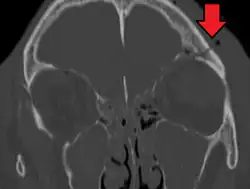

Basilar skull fracture

A basilar skull fracture is a break of a bone in the base of the skull.[1] Symptoms may include bruising behind the ears, bruising around the eyes, or blood behind the ear drum.[1] A cerebrospinal fluid (CSF) leak occurs in about 20% of cases and may result in fluid leaking from the nose or ear.[1] Meningitis occurs in about 14% of cases.[2] Other complications include injuries to the cranial nerves or blood vessels.[1]

A basilar skull fracture typically requires a significant degree of trauma to occur.[1] It is defined as a fracture of one or more of the temporal, occipital, sphenoid, frontal or ethmoid bone.[1] Basilar skull fractures are divided into anterior fossa, middle fossa and posterior fossa fractures.[1] Facial fractures often also occur.[1] Diagnosis is typically by CT scan.[1]

Basilar skull fractures include breaks in the posterior skull base or anterior skull base. The former involve the occipital bone, temporal bone, and portions of the sphenoid bone; the latter, superior portions of the sphenoid and ethmoid bones. The temporal bone fracture is encountered in 75% of all basilar skull fractures and may be longitudinal, transverse or mixed, depending on the course of the fracture line in relation to the longitudinal axis of the pyramid.[5]